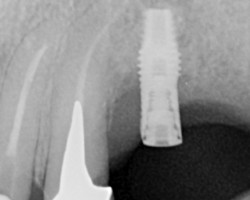

Bone level or Tissue level

S’il est vrai, que pour des raisons de contamination bactérienne, notamment au niveau des micro joints des implants, il est conseillé de mettre ce micro-joint à l’extérieur du niveau osseux, et que le fait d’avoir un col lisse qui place ce micro-joint au-dessus des tissus, l’adhésion des tissus à la surface titane de l’implant est très bonne.

On privilégiera donc un implant avec une connexion interne pseudo cône morse, plutôt rugueux (modéré) pour améliorer l’ostéointégration et avec un col lisse plus ou moins important pour la stabilité des tissus et positionner le micro-joint en dehors de l’os.